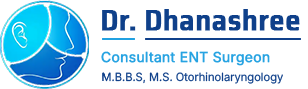

- Ear Wax Removal

- Nasal Endoscopy